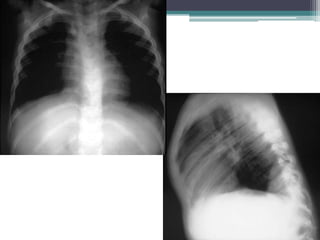

Eight year old male with a

โ–ซ PA and lateral chest films show a

large anterior mediastinal mass

causing narrowing and rightward

deviation of the trachea. The

mass is not calcified.